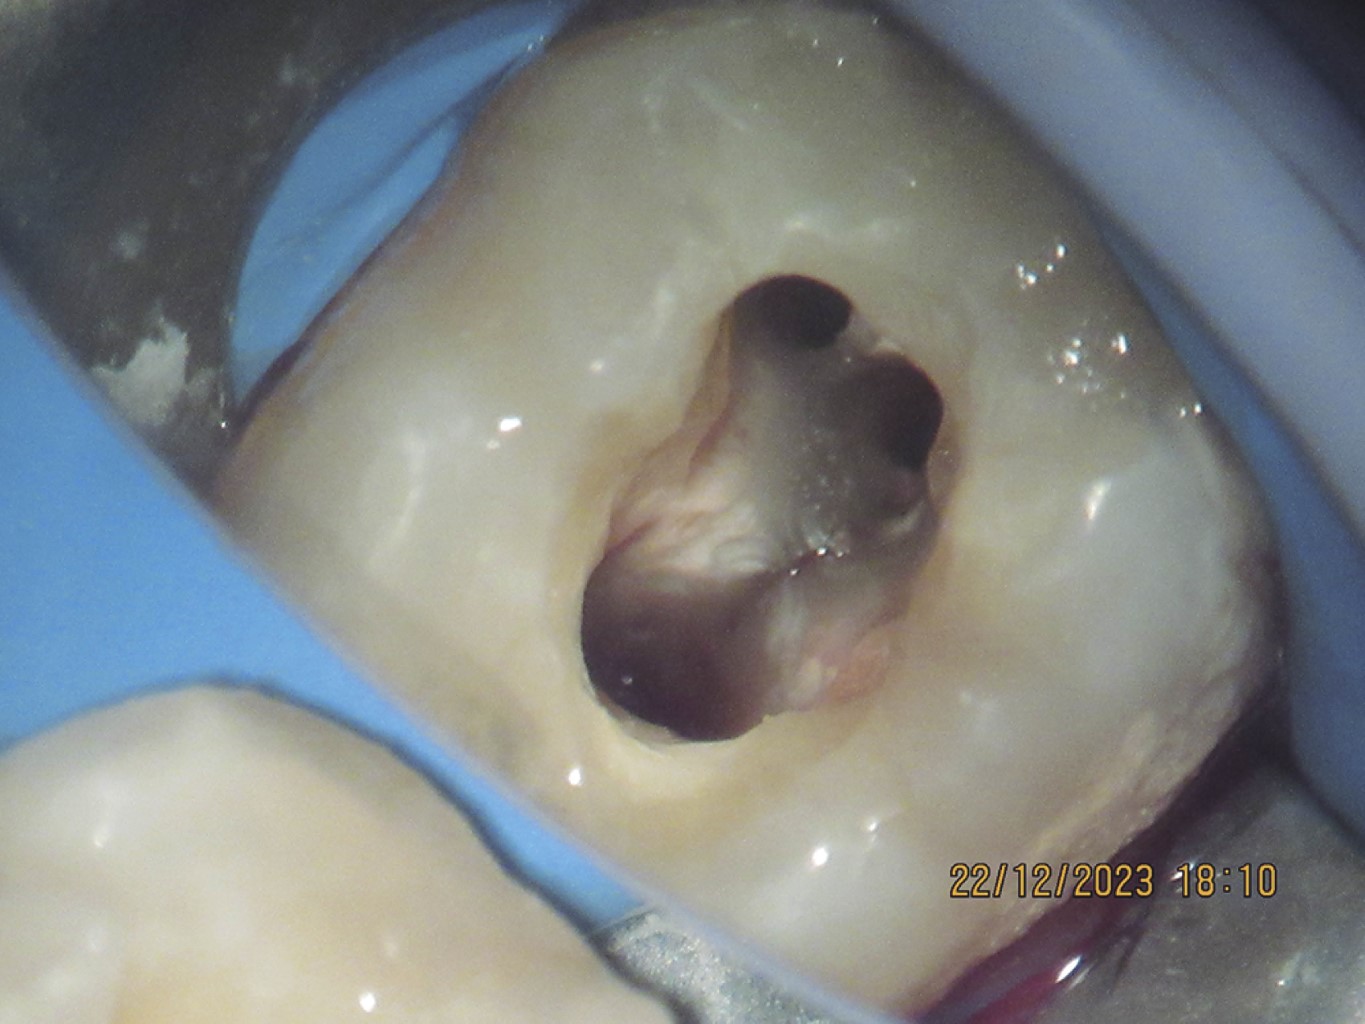

Las imágenes de reconstrucción 3D muestran pérdida de cortical vestibular en la zona del tercer molar, de forma redondeada, compatible con la forma de la corona del tercer molar extraído previamente, así como reabsorción de los tercios medio y apical de la raíz distal del segundo molar, observando que la reabsorción no se presenta de forma simétrica, la pared lingual de la raíz se extiende aproximadamente al tercio medio, no así la pared vestibular de la misma raíz que solamente está presente hasta el tercio coronal (Figuras 3 y 4).

La proyección coronal de la tomografía comprueba lo anterior, además muestra un conducto distal amplio que se extiende solamente hasta el tercio coronal radicular (Figura 5).

Por su parte, en la proyección sagital se observa que la pared mesial de la raíz distal termina aproximadamente en el tercio medio radicular y la pared distal tiene su nivel en el tercio coronal (Figura 6).

Figura 3

Figura 4

Figura 5

Figura 6